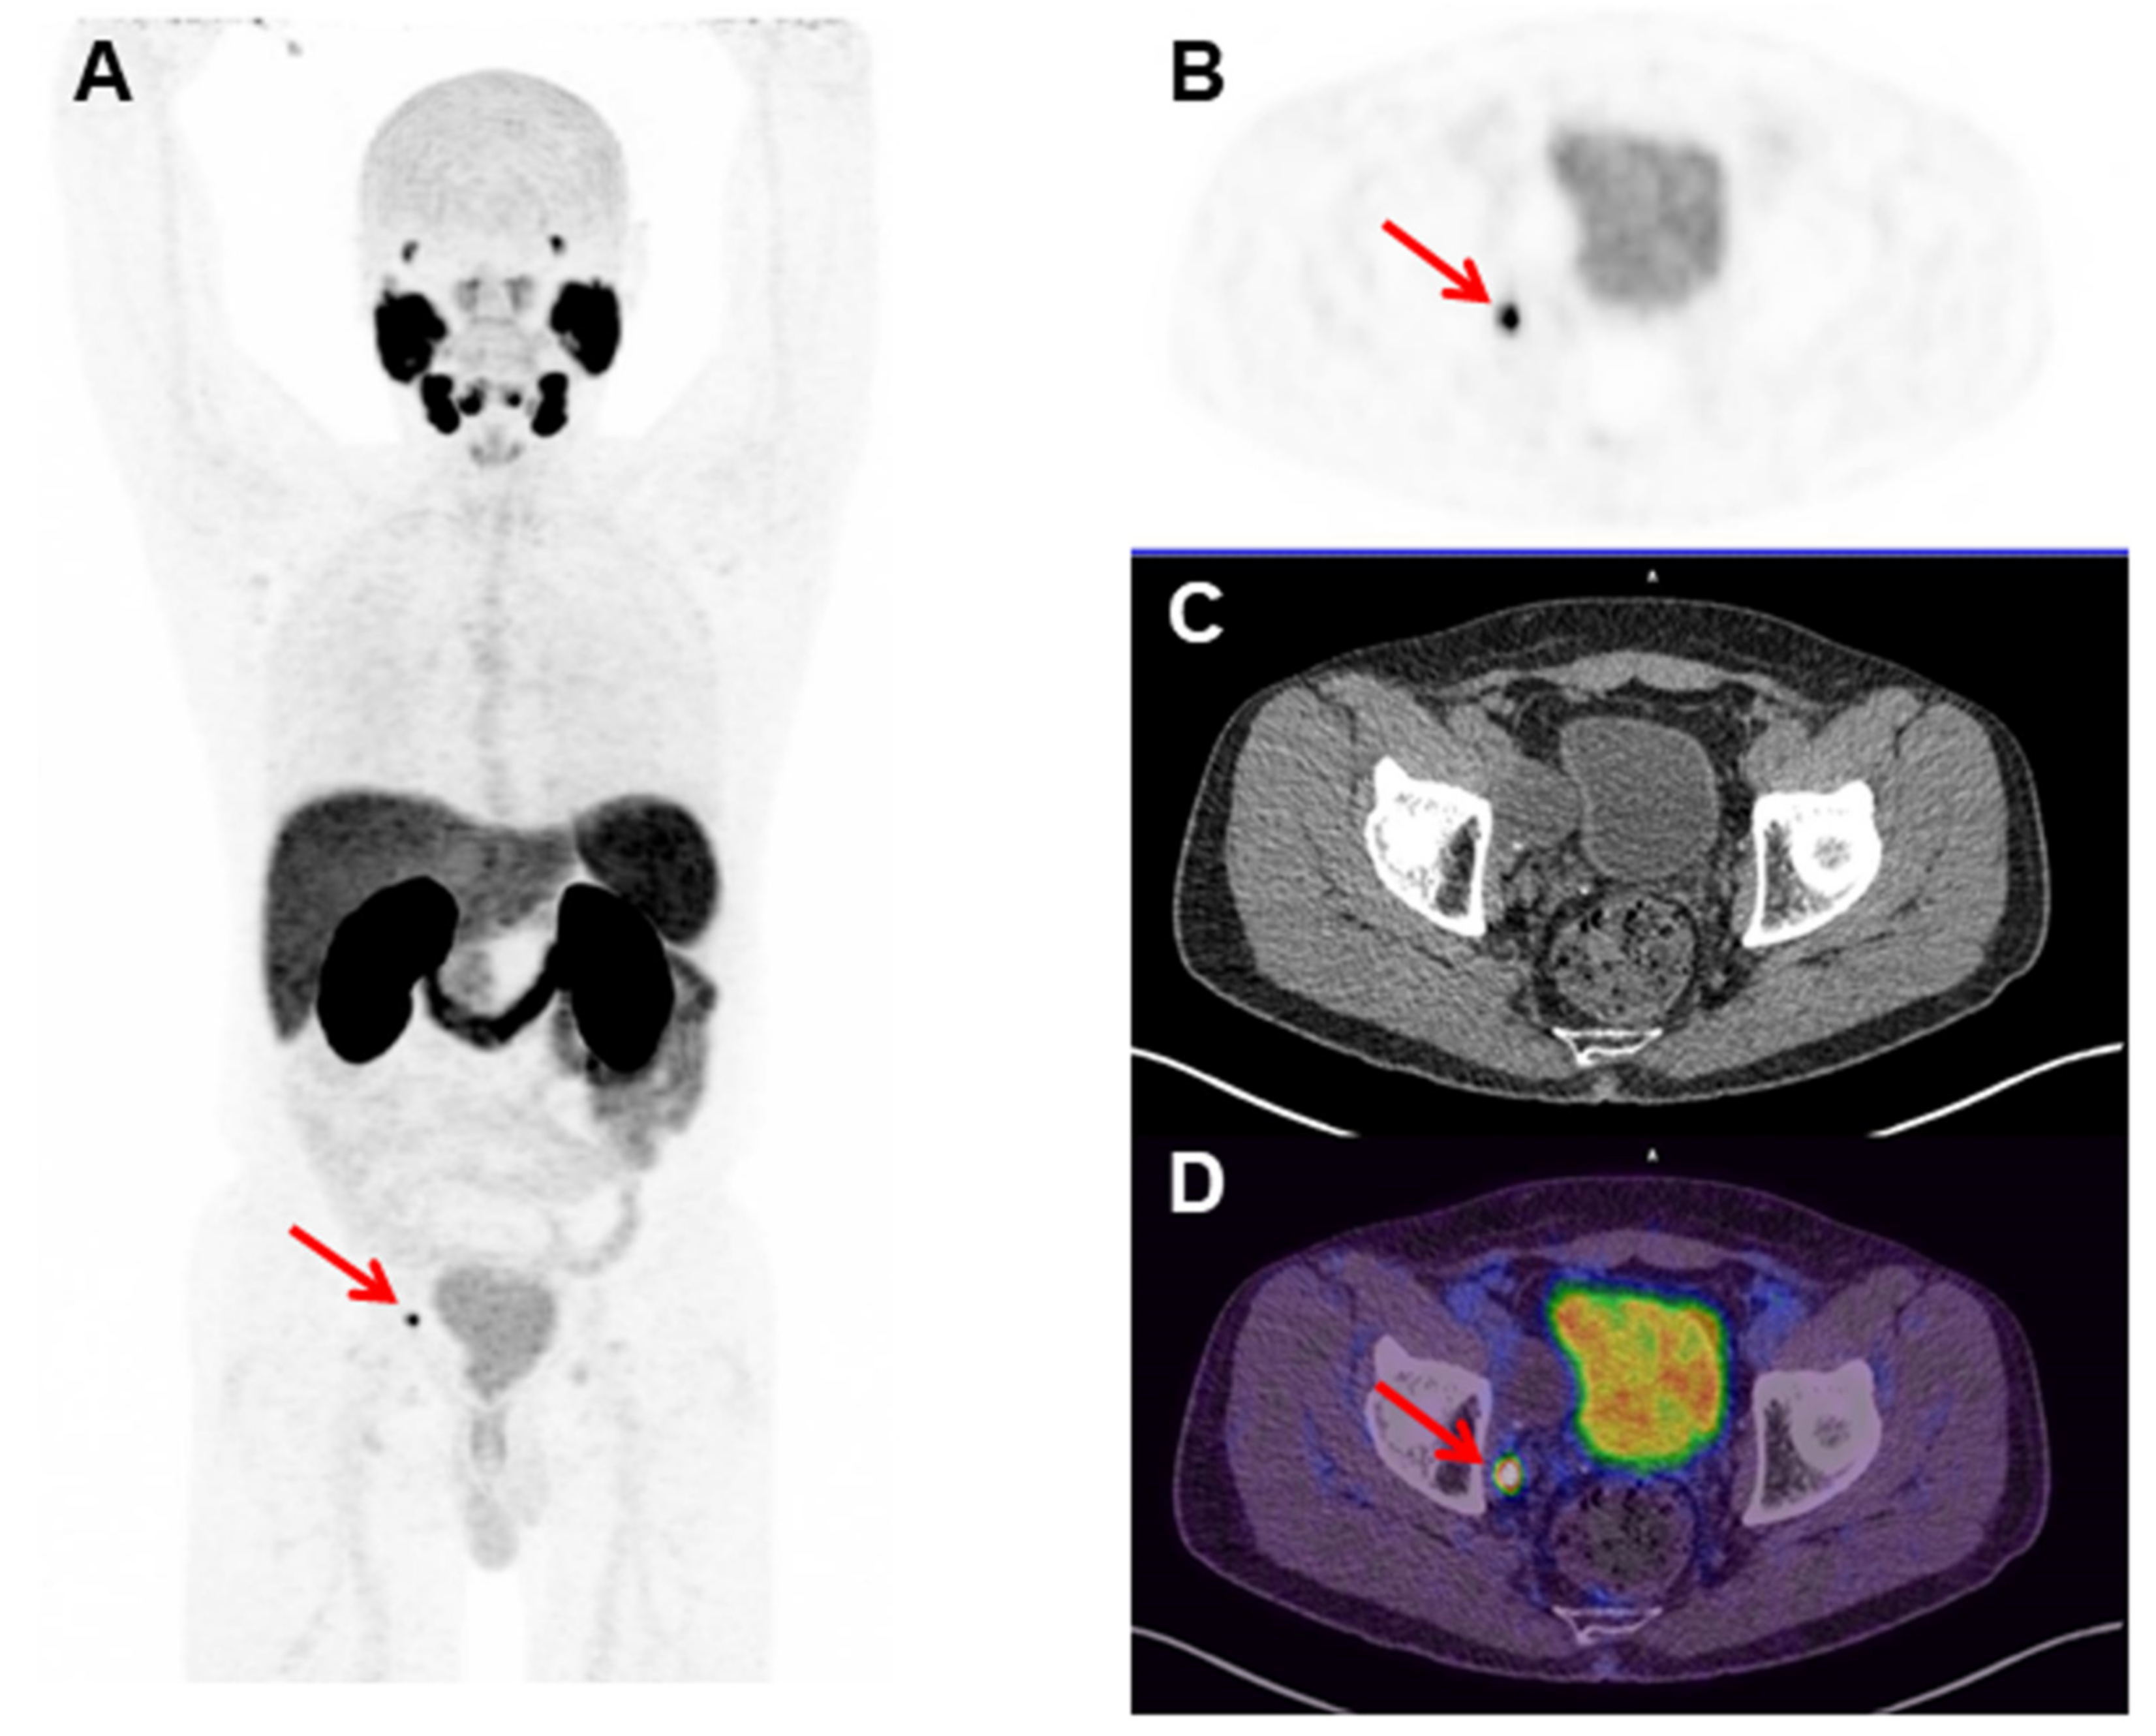

- da Cunha, M.L.; Rodrigues, C.d.O.; de Araújo, M.P.L.; de Freitas Junior, C.H.; Ferrigno, R. Solitary testicular metastasis from prostate cancer. A case report diagnosed by PET/CT with PSMA. Eur. J. Nucl. Med. Mol. Imaging 2018, 45, 888–889. [Google Scholar] [CrossRef]

- Ringheim, A.; Campos Neto, G.C.; Anazodo, U.; Cui, L.; da Cunha, M.L.; Vitor, T.; Martins, K.M.; Miranda, A.C.C.; De Barboza, M.F.; Fuscaldi, L.L.; et al. Kinetic modeling of 68Ga-PSMA-11 and validation of simplified methods for quantification in primary prostate cancer patients. EJNMMI Res. 2020, 10, 12. [Google Scholar] [CrossRef]

- Afshar-Oromieh, A.; da Cunha, M.L.; Wagner, J.; Haberkorn, U.; Debus, N.; Weber, W.; Eiber, M.; Holland-Letz, T.; Rauscher, I. Performance of [68Ga]Ga-PSMA-11 PET/CT in patients with recurrent prostate cancer after prostatectomy—a multi-centre evaluation of 2533 patients. Eur. J. Nucl. Med. Mol. Imaging 2021, 1–10. [Google Scholar] [CrossRef]